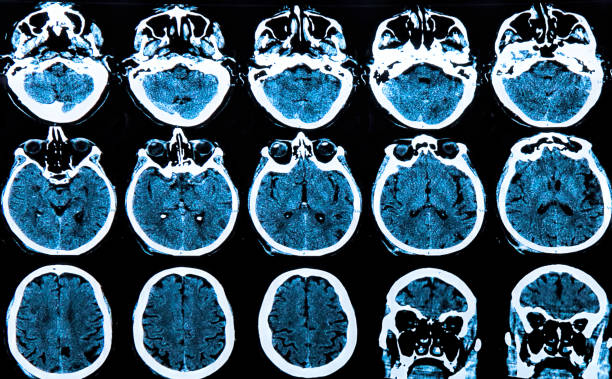

Esta evolución hacia la neurociencia virtual ha llevado consigo una revolución en la forma en que comprendemos el cerebro. Además, la generación de mapas cerebrales digitales y la aplicación de diferentes tecnologías, se ha convertido en una herramienta esencial para abordar la creciente prevalencia de enfermedades neurológicas.

Finalmente, ha contado con la capacidad de visualizar el cerebro con una resolución de células individuales, llegando a crear hasta mapas digitales tridimensionales. Lo que ha supuesto que abriera nuevas puertas para el estudio de trastornos neurológicos y metabólicos (Perens y Hecksher-Sørensen, 2022).

Mapeo cerebral: Indagando en el cerebro

Como mencionamos anteriormente, el mapeo cerebral permite identificar las áreas funcionales del cerebro humano. Esta técnica esencial en la neurocirugía contemporáne tiene como objetivo trazar un mapa detallado de las regiones cerebrales que controlan funciones específicas, como el movimiento, lenguaje, percepción y cognición. Lo anterior, lo realiza a través de distintas formas. Pueden ser métodos invasivos, como la estimulación eléctrica directa, o tambíen técnicas no invasivas como la resonancia magnética funcional y la magnetoencefalografía.

Dicha herramienta ha evolucionado significativamente a lo largo del tiempo, y las técnicas no invasivas están desempeñando un papel cada vez más importante debido a su comodidad y seguridad para los pacientes. Además, el conocimiento generado a través del mapeo cerebral no solo beneficia a la neurocirugía, sino que también ha contribuido al entendimiento de enfermedades neurológicas y trastornos cognitivos (Perens y Hecksher-Sørensen, 2022).

Cartografía cerebral funcional

Una de las ventajas más notables de la neurociencia virtual es su capacidad para representar el mapeo cerebral en tres dimensiones. Además, esto permite a los investigadores explorar las estructuras cerebrales y las conexiones neuronales con un nivel de detalle sin precedentes. Pues los modelos digitales facilitan el desglose del cerebro en regiones específicas y visualizar cómo interactúan entre sí.